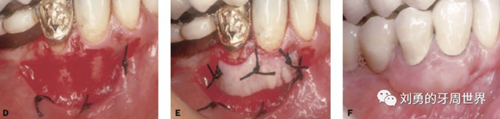

比如下面兩張圖就分別是縫合和剪掉的方法:

第五個要說的改良就是受區(qū)半厚瓣的改良,一種使用手術(shù)刀翻開半厚瓣,暴露骨膜床的方式,該方法操作起來困難尤其是后牙區(qū)域,另外一種方式是用高速手機(jī)金剛砂車針大量噴水磨除受區(qū)表皮組織的方法來暴露骨膜床,該方法操作簡單粗暴,出血多。如下圖: